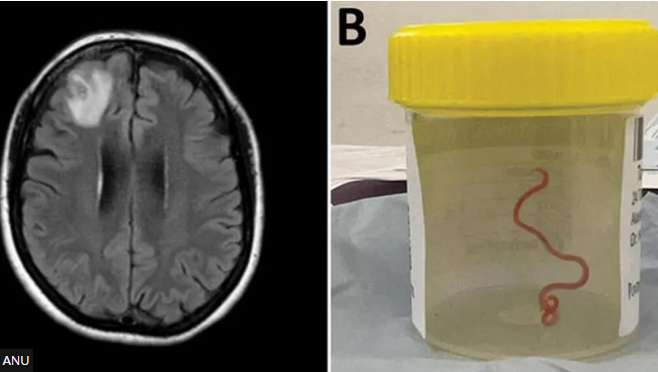

In a world first, scientists say an 8cm (3in) worm has been found alive in the brain of an Australian woman.

The "string-like structure" was pulled from the patient's damaged frontal lobe during surgery in Canberra last year.

She was admitted to hospital in late January 2021, and a scan later revealed "an atypical lesion within the right frontal lobe of the brain".

But the cause of her condition was only revealed by Dr Bandi's knife during a biopsy in June 2022.

The red parasite could have been alive in her brain for up to two months, doctors said.

Her case is believed to be the first instance of a larvae invasion and development in the human brain, researchers said in the Emerging Infectious Diseases journal which reported the case.

"Everyone [in] that operating theatre got the shock of their life when [the surgeon] took some forceps to pick up an abnormality and the abnormality turned out to be a wriggling, live 8cm light red worm," said Dr Senanayake.